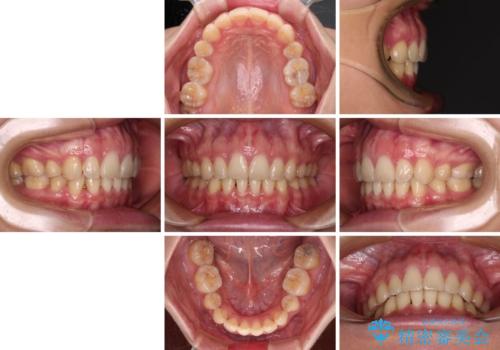

上顎前突 目立たないワイヤー装置での抜歯矯正

- 口元の突出感改善を希望して来院された患者様です。

口元を積極的に引っ込めるために、上下左右の小臼歯計4本を抜歯することとしました。

咬み合わせが深いため、咬み合わせの高さを向上させながら口元を下げることとしました。

左右ともに下顎に対して上顎歯列が前方位にある上顎前突であったので、上顎歯列全体を後方に移動させることで上下咬み合わせを改善し、その上で抜歯矯正により口元の突出感を改善させていきました。